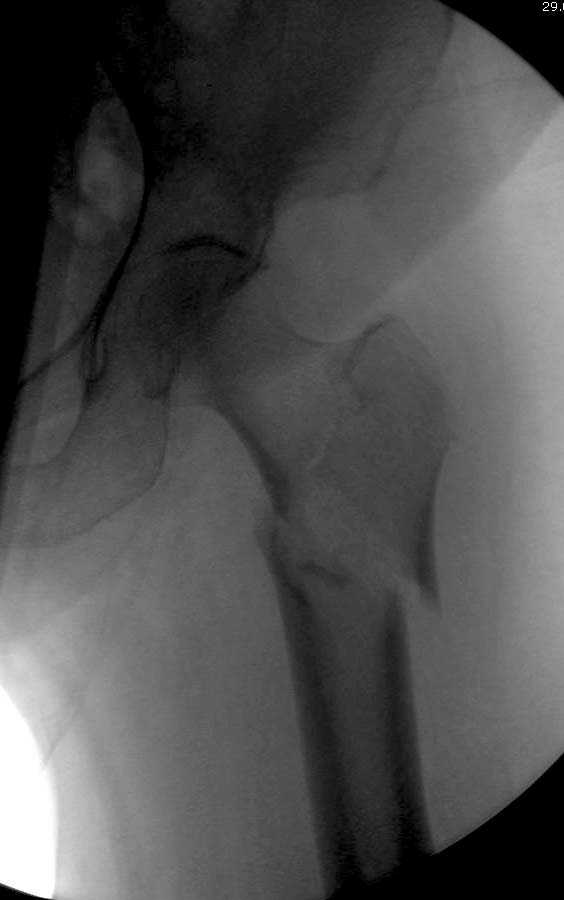

Здесь представлен случай, где в послеоперационном периоде обнаружена техническая ошибка, Gamma 3 установлен с нарушением методики. Больная в 91 лет, прооперирована через день после поступления и выписана через 48 часов.

При первом послеоперационном поликлиническом осмотре больная предъявила жалобы на боли в бедре. В серийных снимках обнаружен продольный перелом верхнего отдела бедра.

Считаем, что техническая ошибка произошла во время установки гвоздя, когда рассверливанию канала не уделили должного внимания. Канал остался узковат, и гвоздь был забит с силой. Полная нагрузка конечности приостановлена на две недели, и боли в конечности изчезли. Больная начала нагрузку и перелом срастается.-- Djoldas Kuldjanov, M.D.Associate ProfessorDepartment of Orthopedic SurgerySt. Louis University

Мне тоже представляется, что это не единственная проблема. Продольные трещины заживают легко и быстро. Интересно, почему увеличился варус и

появилась медиализация дистального отломка.

Мне думается, что варусное положение проксимального отломка на последующих снимках не более чем проекционный феномен. Раскол же диафиза вдоль, наверняка, связан с чрезмерно насильственным введением штифта. Вообще, при реверсивных, да и обычных вертельных переломах, многие давно отказались от короткой Гаммы в пользу long-версии. Но в любом случае надо быть на 100 уверенным в подготовке канала.